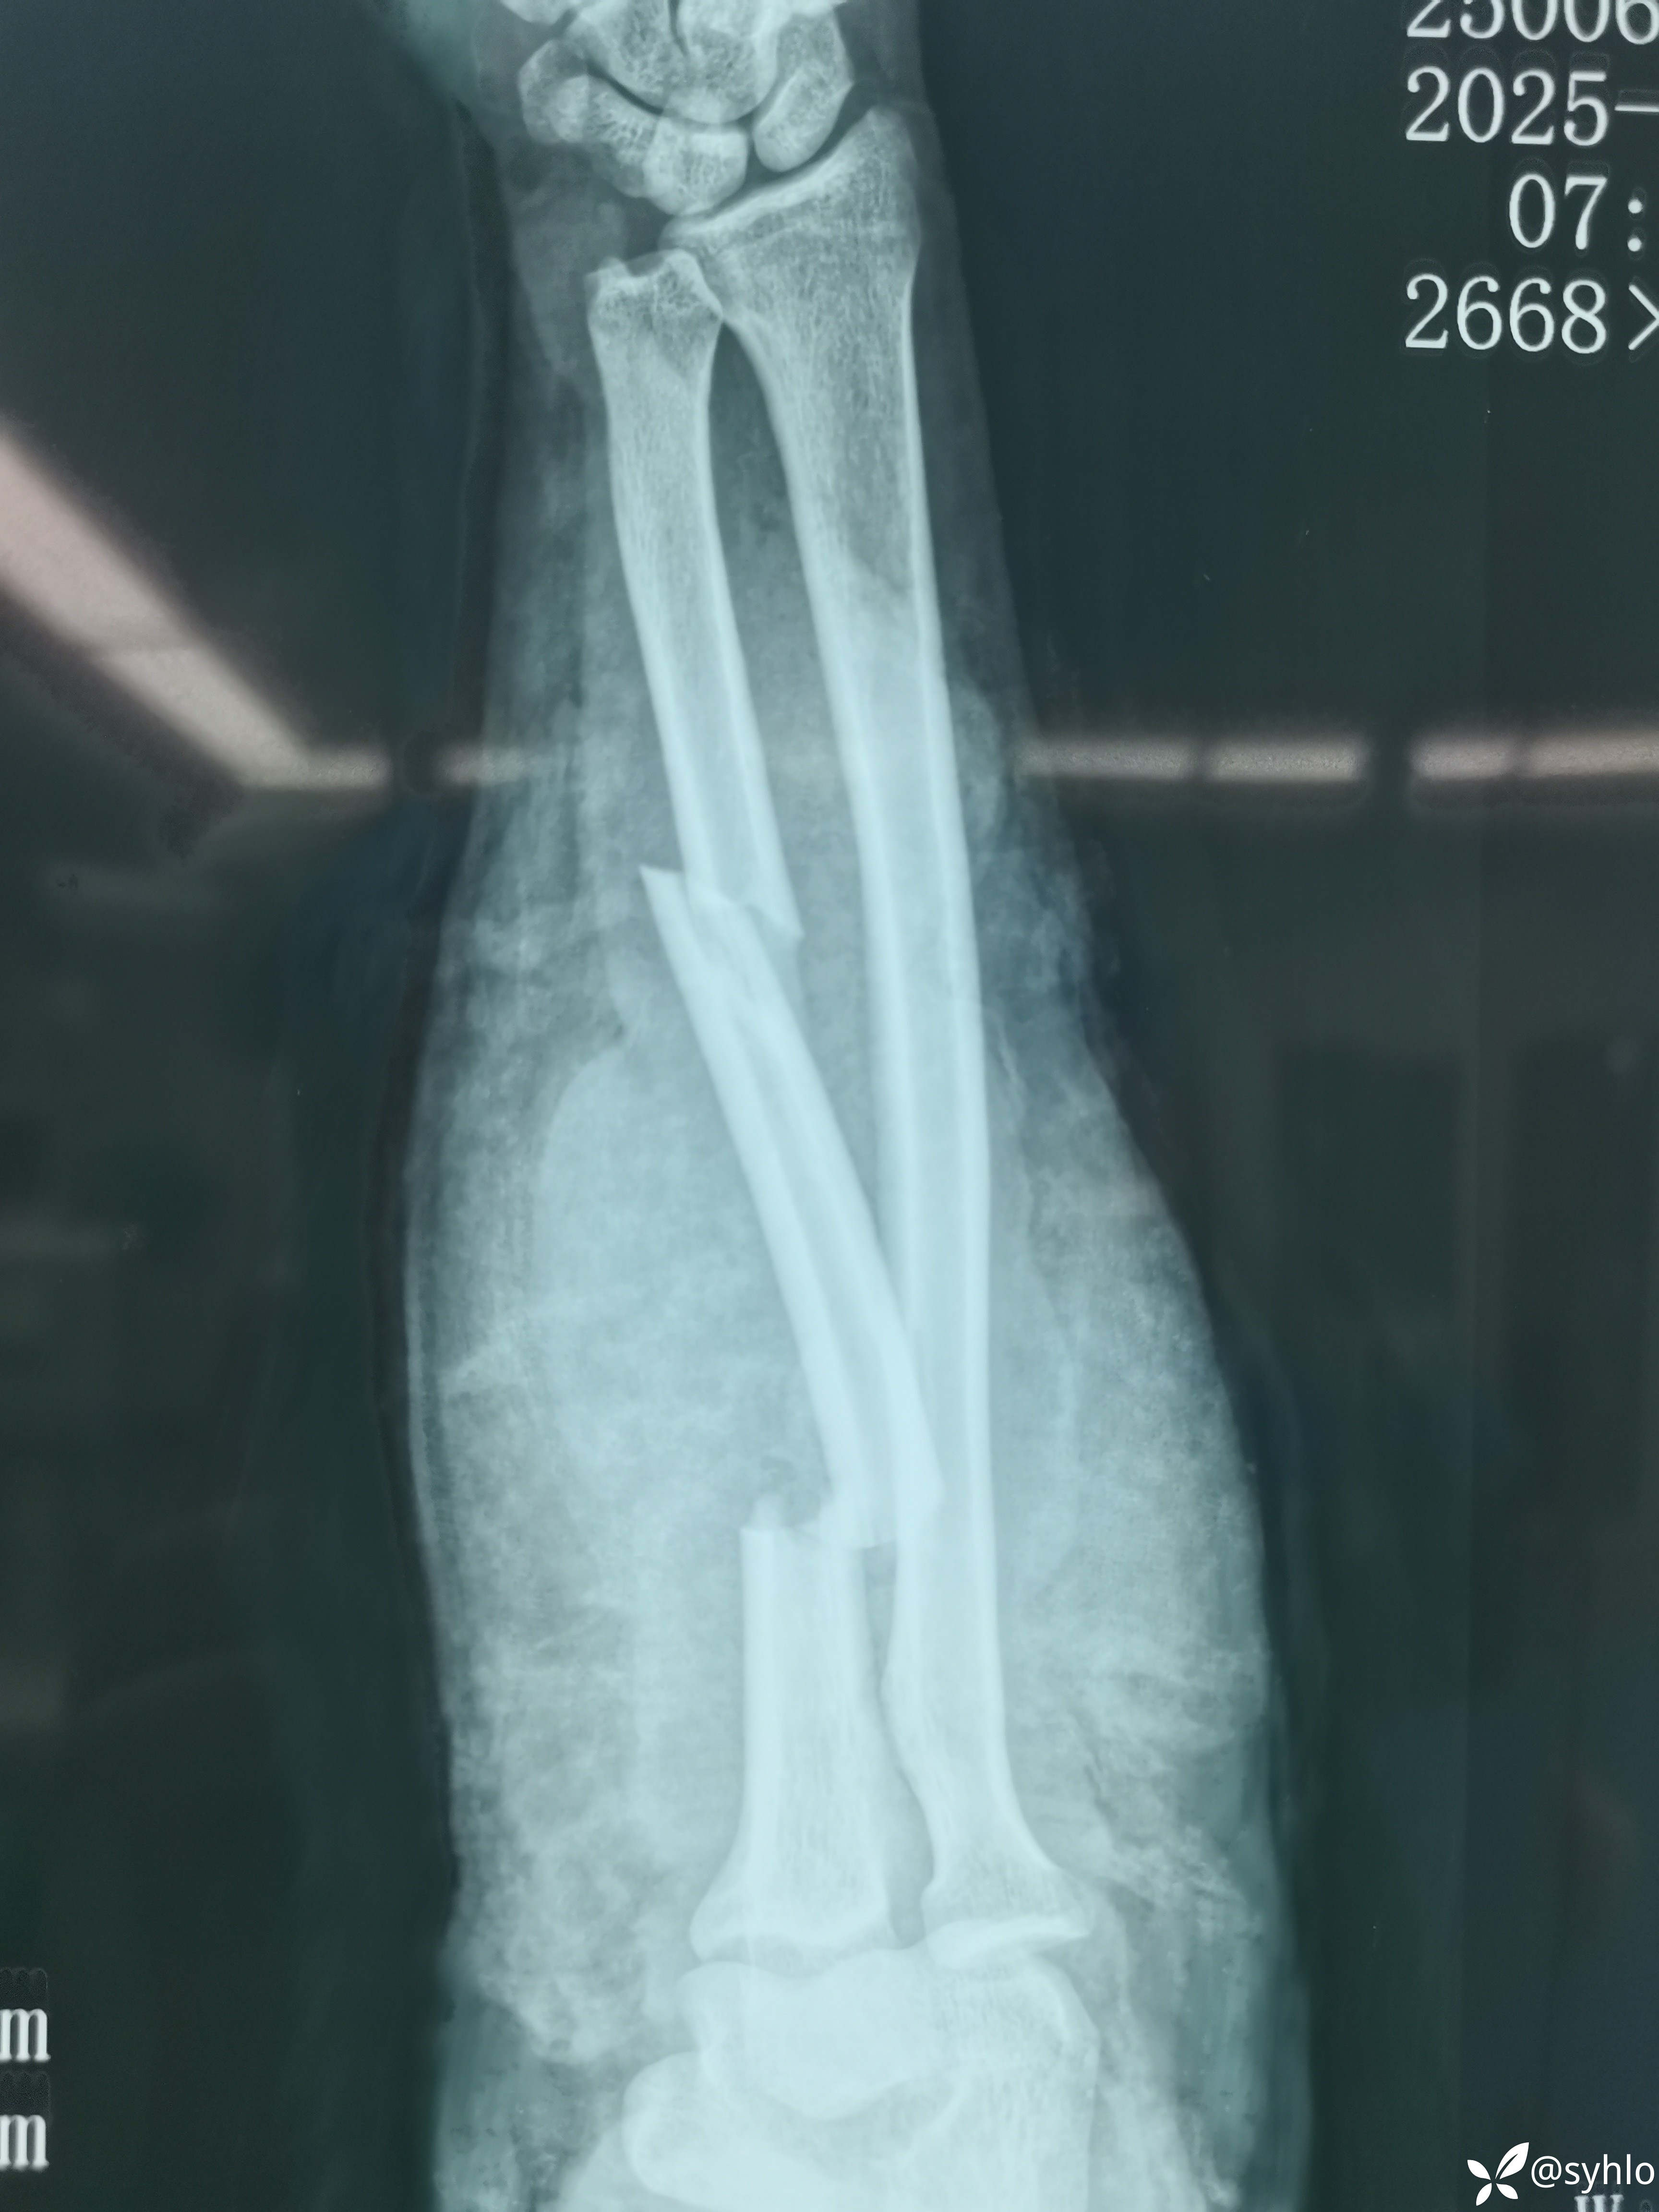

机器搅伤右上肢,缅甸籍贯在中国打工,家庭十分困难,多地辗转建议转省级医院治疗,家庭困难不愿意转。开放性肱骨,尺桡骨,掌骨骨折伴皮肤大面积撕脱。急诊清创外固定架+VSD负压吸引